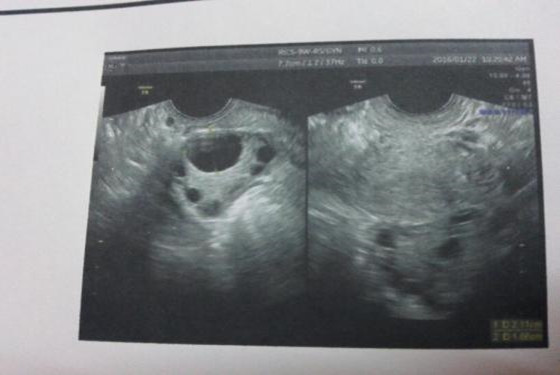

卵泡长得慢,卵泡发育不良,是现如今很多女性都存在的问题,卵泡发育是否良好,关系到能否顺利受孕的问题,所以,这可不是小问题,对于女性来说可是个大难题。关于,如何提高卵泡质量的方法有很多,最近,在网络上看到,关于卵泡长得慢吃黑豆跳绳的热评,赶快来看看。

我是爻爻,备孕快5个月了可是一直没有结果,以前月经周期一直很准的,为了能尽快怀上孩子,也曾跑去医院做过卵泡监测,一次偶然的机会,听闺蜜说吃黑豆+跳绳,能够让卵泡长得又快又好,于是我就报着试一试的心情做做看。